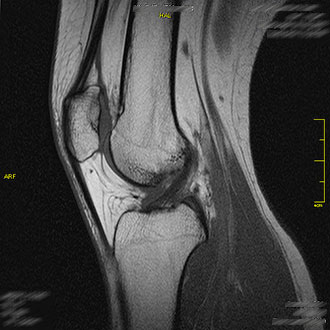

Das Kniegelenk gehört zu den am häufigsten untersuchten Regionen in der MRT.

Im Kernspin Zentrum Köln werden Traumafolgen, Osteochondrosen, Arthrosen oder Meniskusschäden präzise dargestellt.

Die MRT hilft, Risse, Schwellungen oder Knorpelschäden zuverlässig zu erkennen – eine wichtige Grundlage für orthopädische und chirurgische Therapieentscheidungen.